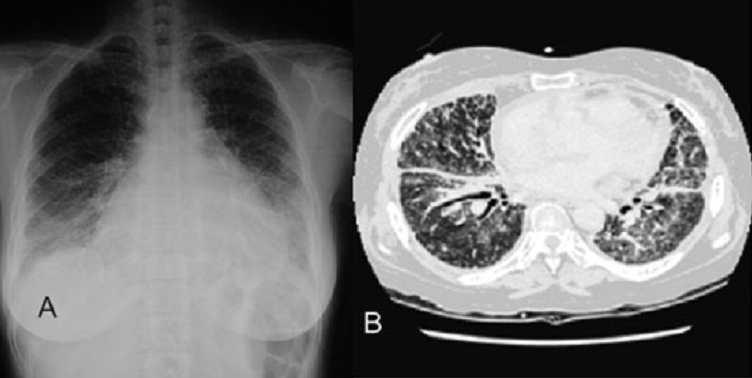

AB: lung image